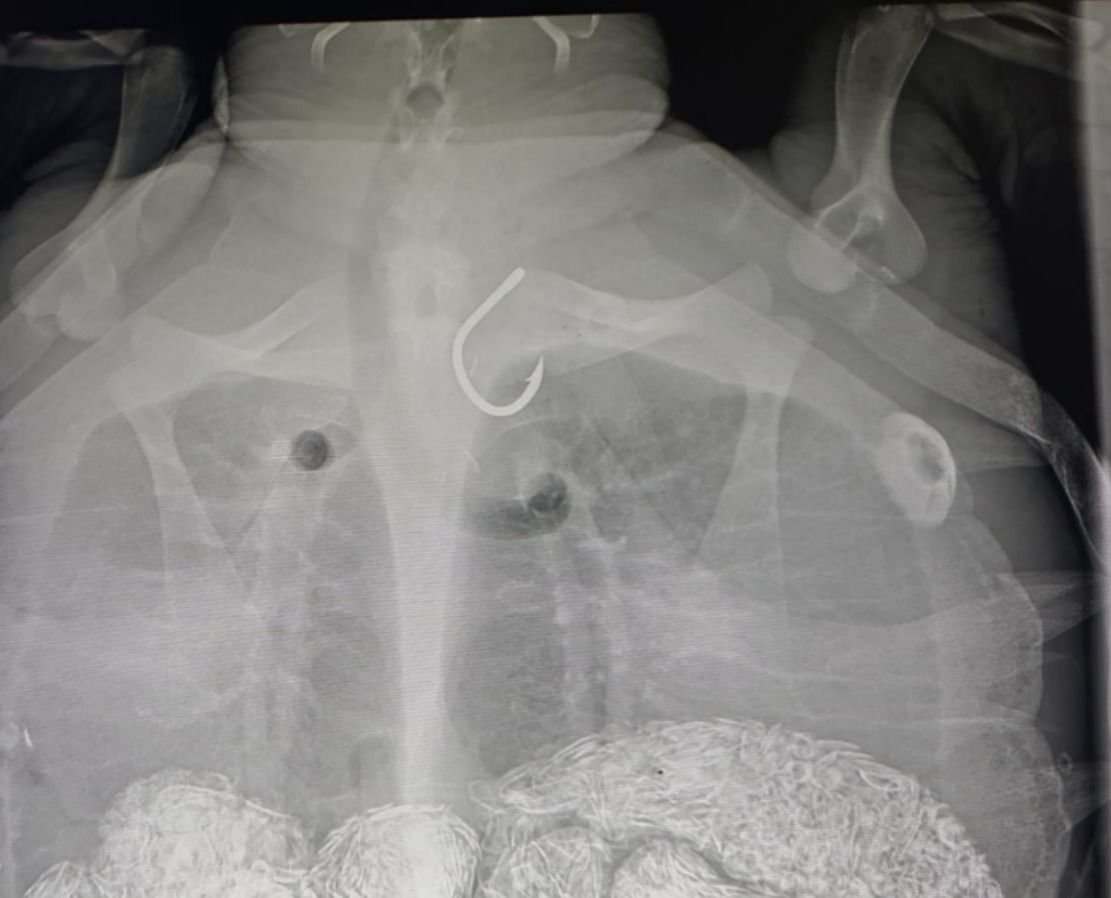

"כשמוצאים צב ים שבלע או הסתבך בקרס דיג, חשוב שלא לחתוך את החוט ולנסות להסיר את הקרס, אלא להביא אלינו את הצב הפצוע ונוכל לסייע לו עם ציוד מתאים בבית החולים שלנו", מסביר גיא אבגי, המטפל הראשי במרכז להצלת צבי ים. "לעיתים רבות צבי הים בולעים קרס נוסף שננעץ באזור הוושט או במערכת העיכול וניתן לגלות זאת רק בצילום רנטגן".

לאחר טיפול תומך והוצאת הקרס, נלקחה נקבקת צב הים לצילומי הדמייה במרפאת "כל חי" ברחובות, שם נדהמו לגלות קרס נוסף גדול שנמצא במערכת העיכול שלה. ד"ר צחי אייזנברג שניתח אותה, הוציא את הקרס בהצלחה.